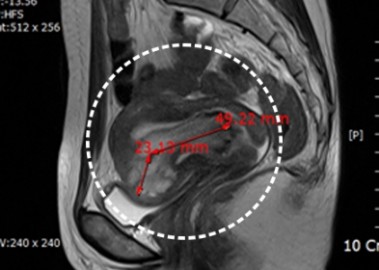

거대 자궁선근증 치료 사례